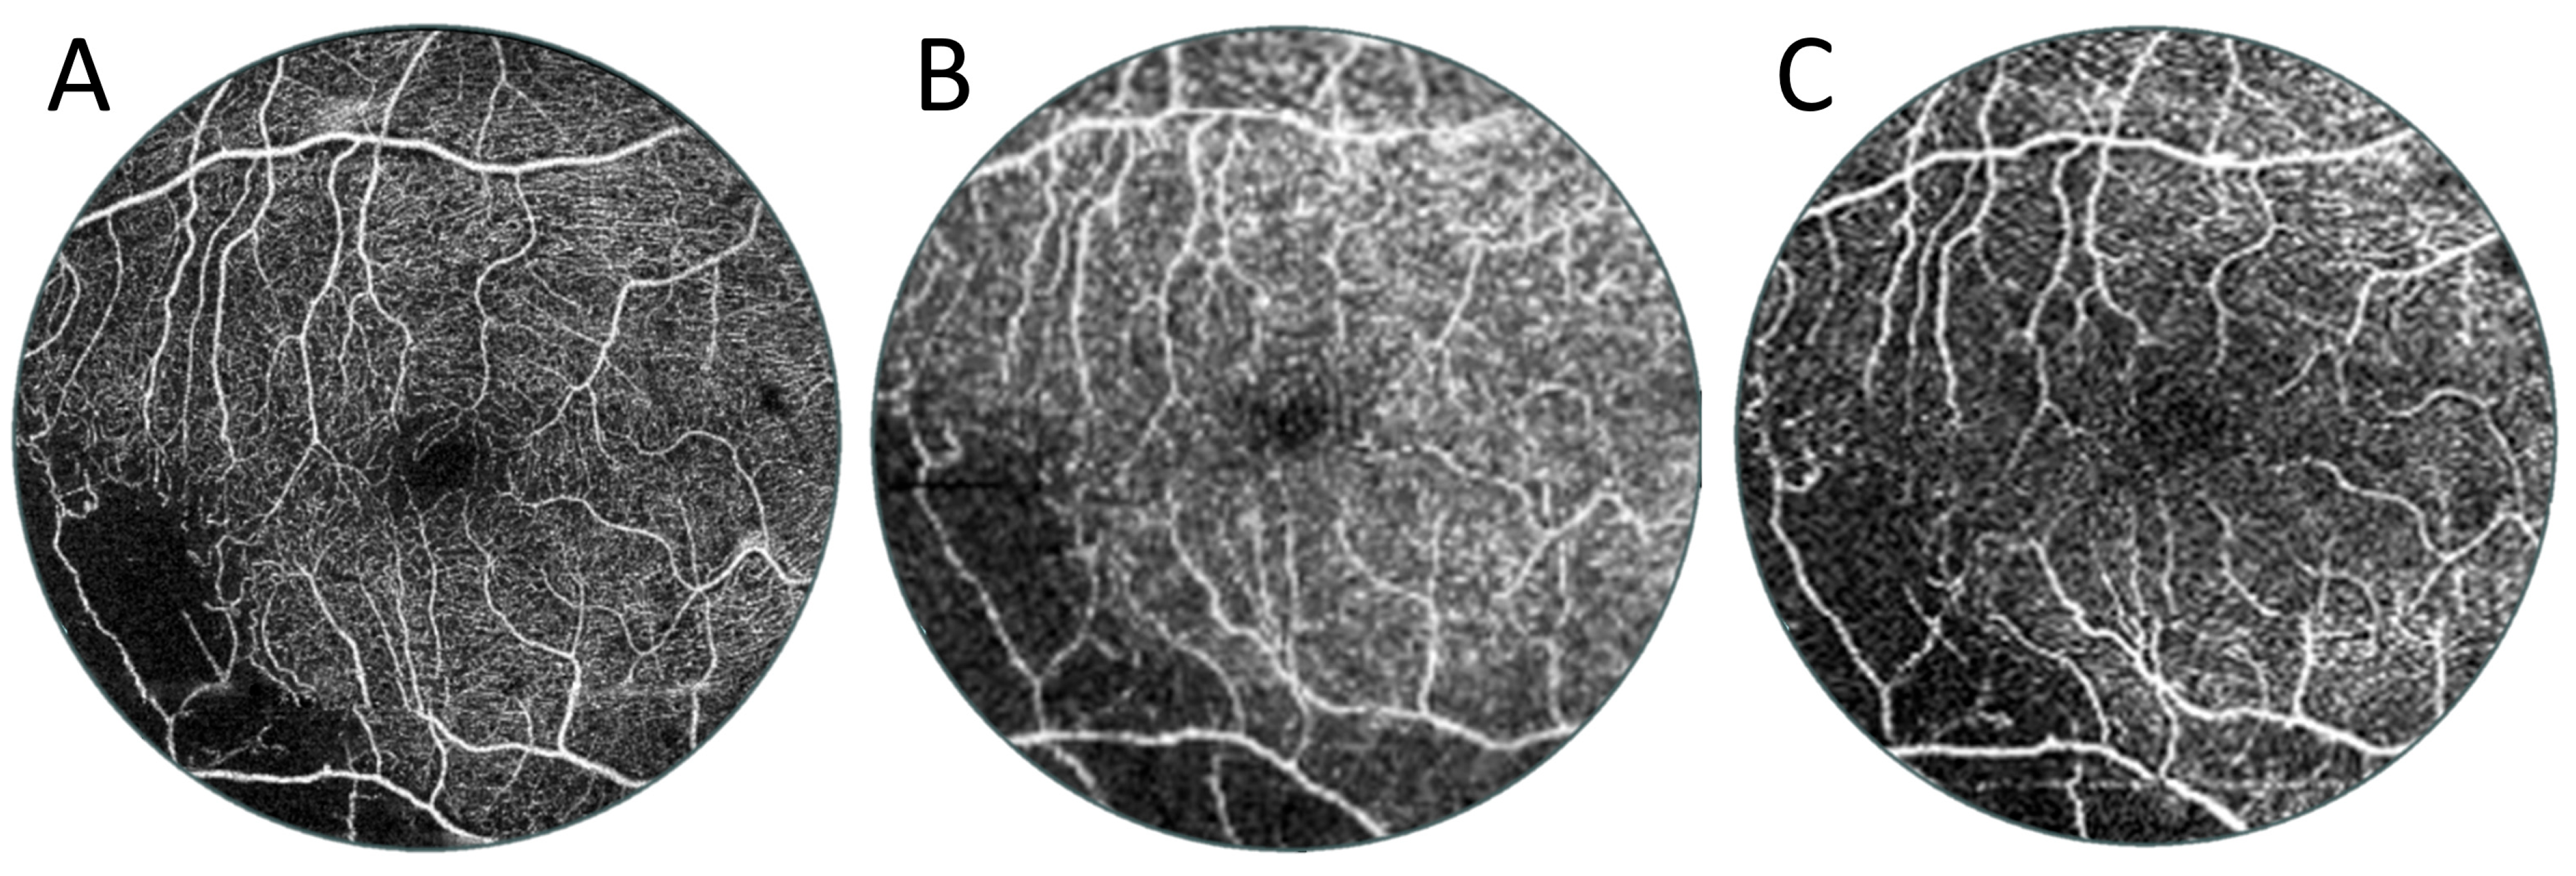

3.2. Angio-OCT Measurements

3.3. OCT and Angio-OCT Measurements